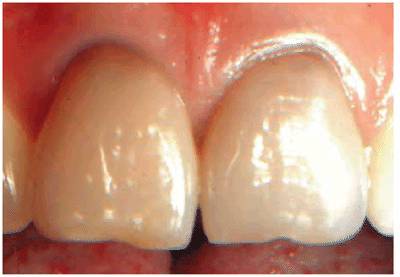

Transillumination via a fiber-optic light may be of great assistance in

detecting color shifts in a crown (Figures 19-1A, and 19-1B). A tooth with a pink or reddish

hue would more than likely indicate internal hemorrhage from a recent injury (Figure 19-2), a dental procedure (Figure 19-3), or gingival tissue hyperplasia

Figure 19-1A: Transillumination of a maxillary left central incisor with a necrotic pulp.

Figure 19-1B: Transillumination of the adjacent tooth with a vital pulp. Because there is active blood flow through the live pulp tissue, the tooth appears brighter to the fiber-optic light than the adjacent tooth with a necrotic pulp.

Figure 19-4A: Pink spot as a result of external resorption.

Figure 19-4B: Radiograph of the same tooth showing external resorption.

Figure 19-4C: Pink spot as a result of internal resorption.

Figure 19-4D: Radiograph of the same tooth showing internal resorption.